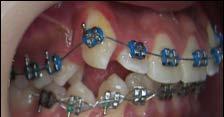

Tratamiento de caninos retenidos superiores en paciente en crecimiento con clase II división 2. Reporte de caso clínico

Los caninos retenidos constituyen una alteración eruptiva frecuente, con mayor prevalencia en la arcada superior. Su etiología es multifactorial y puede interferir con el trayecto normal de erupción, comprometiendo la oclusión y la estética.

Objetivo: Corregir una maloclusión Clase II división 2 mediante tratamiento ortodóntico en un paciente en crecimiento con ambos caninos superiores retenidos. Metodología: Se presenta el caso de un paciente masculino de 12 años, en dentición permanente, con perfil convexo, patrón dolicofacial y Clase II esquelética. Se realizó tratamiento ortodóntico sin extracciones. Para la tracción y alineación de los caninos retenidos se emplearon resortes abiertos (open coil springs) para la creación de espacio. Resultados: